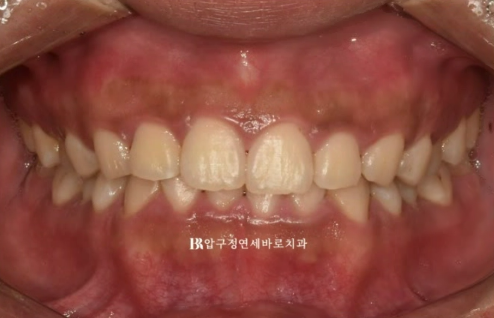

웃을 때 왼쪽 치아가 내려와 보인다라는 이유로 교정치료를 위해 찾아오신 환자분입니다.

윗니가 아랫니를 너무 많이 덮는 것을 과개교합 이라고 합니다.

아랫니는 거의 안 보입니다.

실제로 웃는 사진에서 교합평면이 기울어져 있는 것이 보입니다.

환자분의 왼쪽 치아들이 더 아래로 내려가 있습니다.